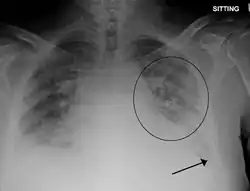

Pulmonary edema with small pleural effusions on both sides

Chest X-ray has been used for many years to diagnose pulmonary edema due to its wide availability and relatively cheap cost.[4] A chest X-ray will show fluid in the alveolar walls, Kerley B lines, increased vascular shadowing in a classical batwing peri-hilum pattern, upper lobe diversion (biased blood flow to the superior parts instead of inferior parts of the lung), and possibly pleural effusions. In contrast, patchy alveolar infiltrates are more typically associated with noncardiogenic edema.[3]